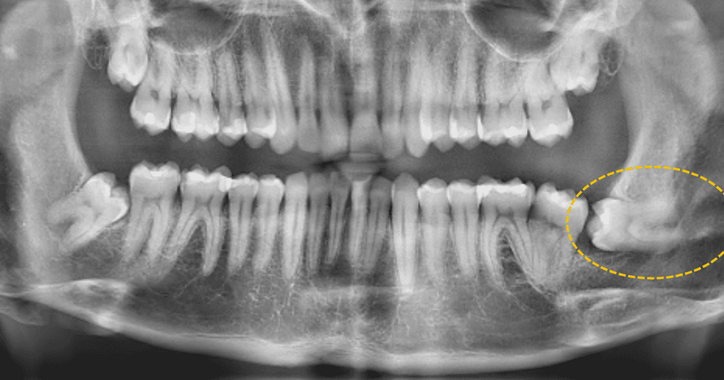

wisdom tooth surgical extraction.png

Wisdom tooth extraction presents a range of complexities. Lower wisdom teeth in particular can be close to major nerves or buried in the jaw bone. Difficult extractions can be referred to specialist Oral Surgeons and performed under general anaesthetic.